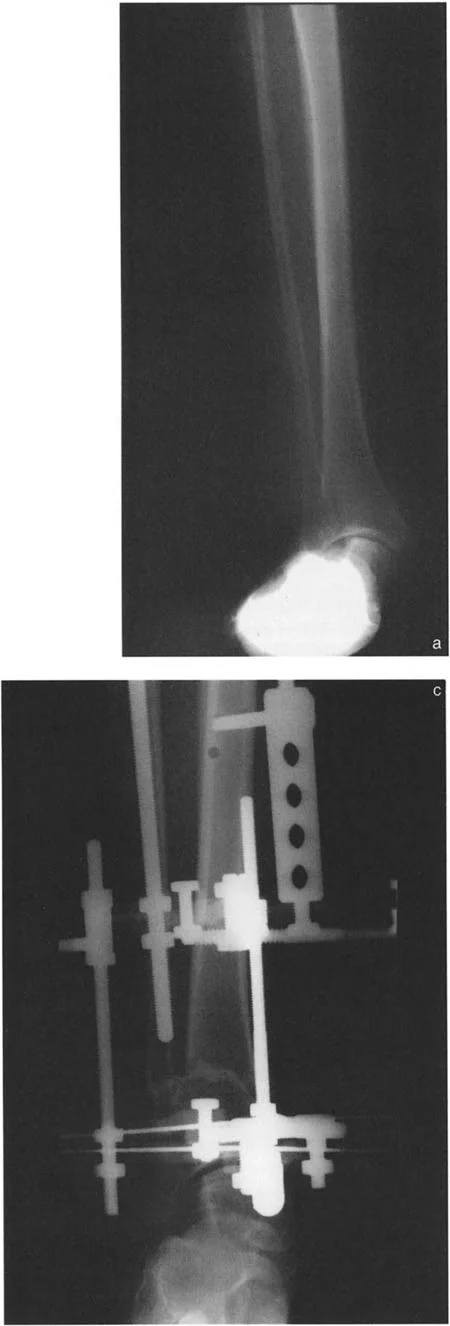

أنواع جراحات قطع العظم فوق الكاحل (Supramalleolar Osteotomy)

جراحة قطع العظم فوق الكاحل (SMO) هي الإجراء الأكثر شيوعًا لتصحيح تشوهات قصبة الساق البعيدة. تتضمن هذه الجراحة قطعًا دقيقًا في عظم الساق (القصبة) فوق مفصل الكاحل مباشرة، ثم إعادة محاذاة العظم وتثبيته في الوضع الصحيح. هناك عدة أنواع من هذه الجراحة:

صورة طبية: الاستاذ الدكتور محمد هطيف: دليل شامل لتشوهات قصبة الساق البعيدة والكاحل في صنعاء